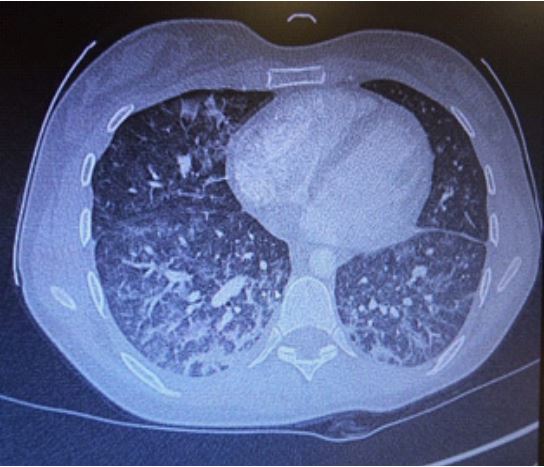

On March 1st, 2021, she started complaining shortness of breath and low-grade fever (37.3°C). Chest x-ray showed interstitial abnormalities and bilateral peripheral infiltrates of the lung basis (Figure 1); a Sars-Cov2 molecular smear was negative. Her General Practitioner started levofloxacin 500 mg daily due to know amoxicillin allergy.

Figure 1: Interstitial abnormalities and bilateral peripheral infiltrates of the lung basis at chest x-ray